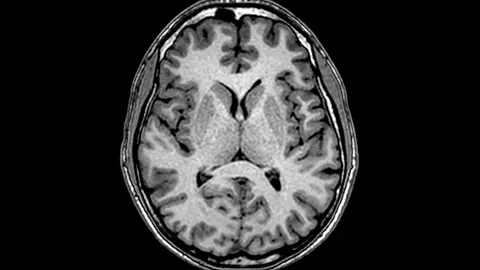

Un estudio realizado en la Universidad de Heidelberg detectó que los jóvenes con un uso intensivo del teléfono presentan una reducción de la materia gris del cerebro en áreas relacionadas con la memoria, la empatía y el autocontrol. Ubicada en la corteza cerebral, la materia gris es un tejido del sistema nervioso central responsable de estas funciones cognitivas.

Según el investigador Christian Montag, estos cambios son comparables a los que se producen en adicciones conductuales. Al mismo tiempo, la OMS alertó de un aumento del 25 % en los casos de ansiedad y depresión durante la pandemia, que además de la soledad provocada en numerosos casos por el aislamiento esto propició que se aumentara el uso y el tiempo ante las pantallas.